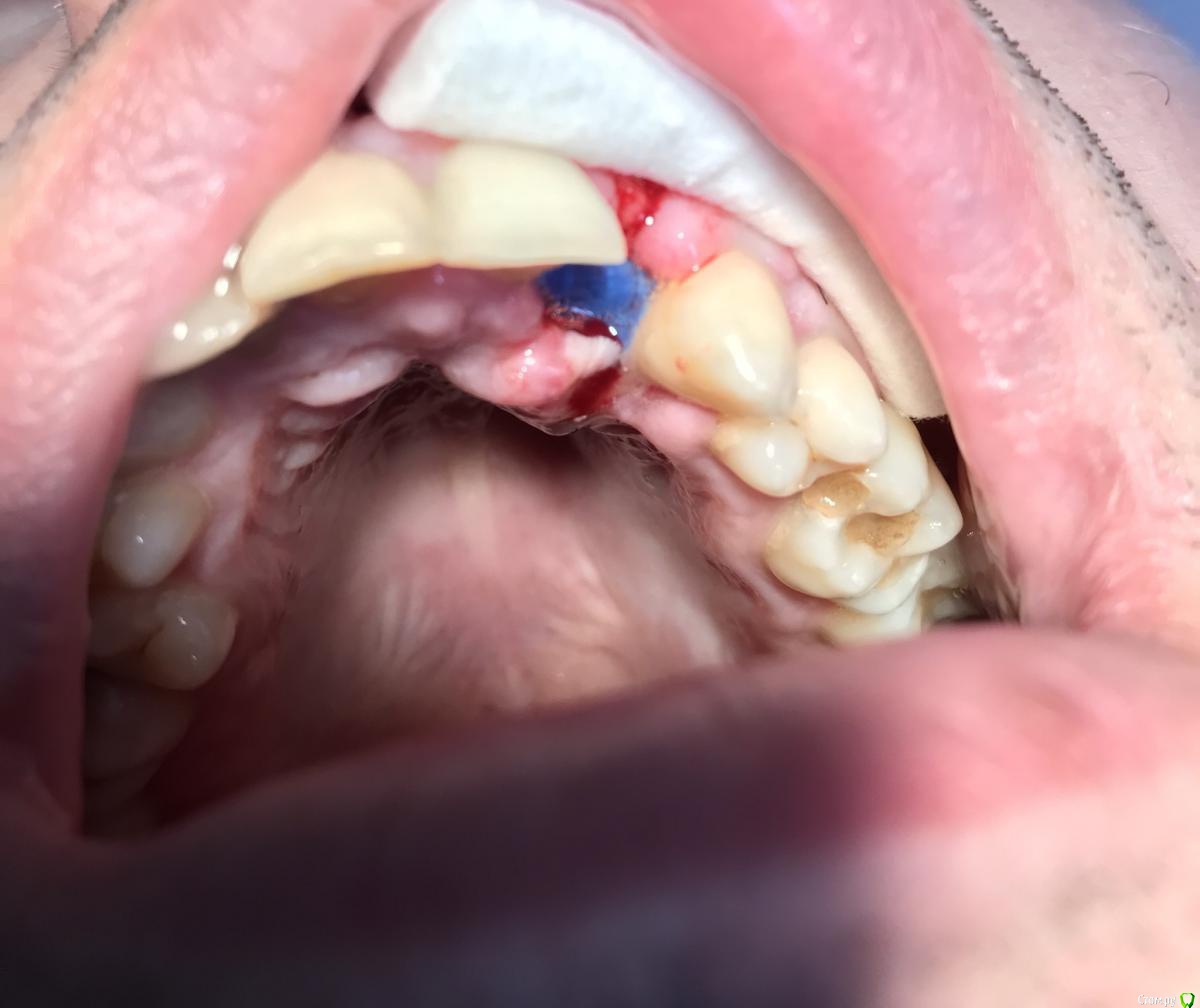

dr.Dre Опубликовано 20 марта, 2019 Поделиться Опубликовано 20 марта, 2019 (изменено) Добрый день коллеги.Сделал НКР с нерезорбируемой мембраной permamem с вестибулярки зафиксировал пином ,небно просто завернул,пациент сегодня пришёл на осмотр, мембрана оголилась ,десна сместилась небно ,после операции прошло 5 дней,гигиена хорошая, как вы ведёте такие ситуации?Читал в книге Иштвана Урбана что данное осложнение бывает ,нужно выждать 6 недель снять мембрану, и зафиксировать коллагеновою и мобилизировать лоскут . Изменено 20 марта, 2019 пользователем dr.Dre Ссылка на комментарий

Борис80 Опубликовано 20 марта, 2019 Поделиться Опубликовано 20 марта, 2019 проблемы прорезывания скрываются в излишнем натяжении слизистой ( часто вследствии недостаточной мобилизации) и недостаточной фиксации лоскута, когда не исключена его подвижность.Надеюсь мембрана у вас была прижата плотно к принимающему ложу? Почему не заколотили пин с небной стороны? Ссылка на комментарий

dr.Dre Опубликовано 20 марта, 2019 Автор Поделиться Опубликовано 20 марта, 2019 проблемы прорезывания скрываются в излишнем натяжении слизистой ( часто вследствии недостаточной мобилизации) и недостаточной фиксации лоскута, когда не исключена его подвижность.Надеюсь мембрана у вас была прижата плотно к принимающему ложу? Почему не заколотили пин с небной стороны?поставил пин с небной соскочил и сорвало кусочек мембраны,решил оставить так Ссылка на комментарий

Nazim_NV86 Опубликовано 21 марта, 2019 Поделиться Опубликовано 21 марта, 2019 В дополнение того, что сказано. На мой скромный взляд дизайн разреза я бы не делал строго по гребню, а сместил бы вестибулярнее. Так швы смещаются с области наибольшего натяжения/разрыва. И второе - шов Бузера делаю в таких ситуациях. Ссылка на комментарий

dr.Dre Опубликовано 26 марта, 2019 Автор Поделиться Опубликовано 26 марта, 2019 Вроде ткань наростает Ссылка на комментарий

syrovovec Опубликовано 29 марта, 2019 Поделиться Опубликовано 29 марта, 2019 Фото не самые удачные, но я за все убрать, пока хуже не стало, вроде и небно рецессия....расстояние между корнями маленькое, и если мембрана и не касается, то очень близко. Ссылка на комментарий